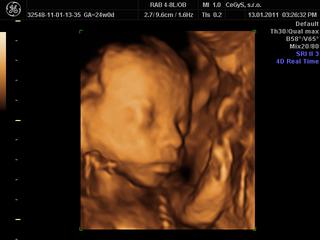

Babule tak sme doma z 3D/4D, mame uzasny zazitok, maly je krasny, podoba sa na naseho Vilka, bradicku, nostek, pusinku maju uplne rovnaku) Dr.bol perfektny, super nam povysvetloval, pokecali sme, venoval sa nam asi hodinku, porobil nam asi 20 fotiek a videii a aj nam vytlacil 1 fotecku, pohral sa s tym, aj nam maleho pomeral, nahodil do tabuliek, proste vsetko mame skoro 800 g a sme tyzden popredu podla malickeho, je to fakz super, mozte sa tesit, mne sa bude dnes o tom urcite snivat) 😵

Pridam vam aj fotecku) 😉